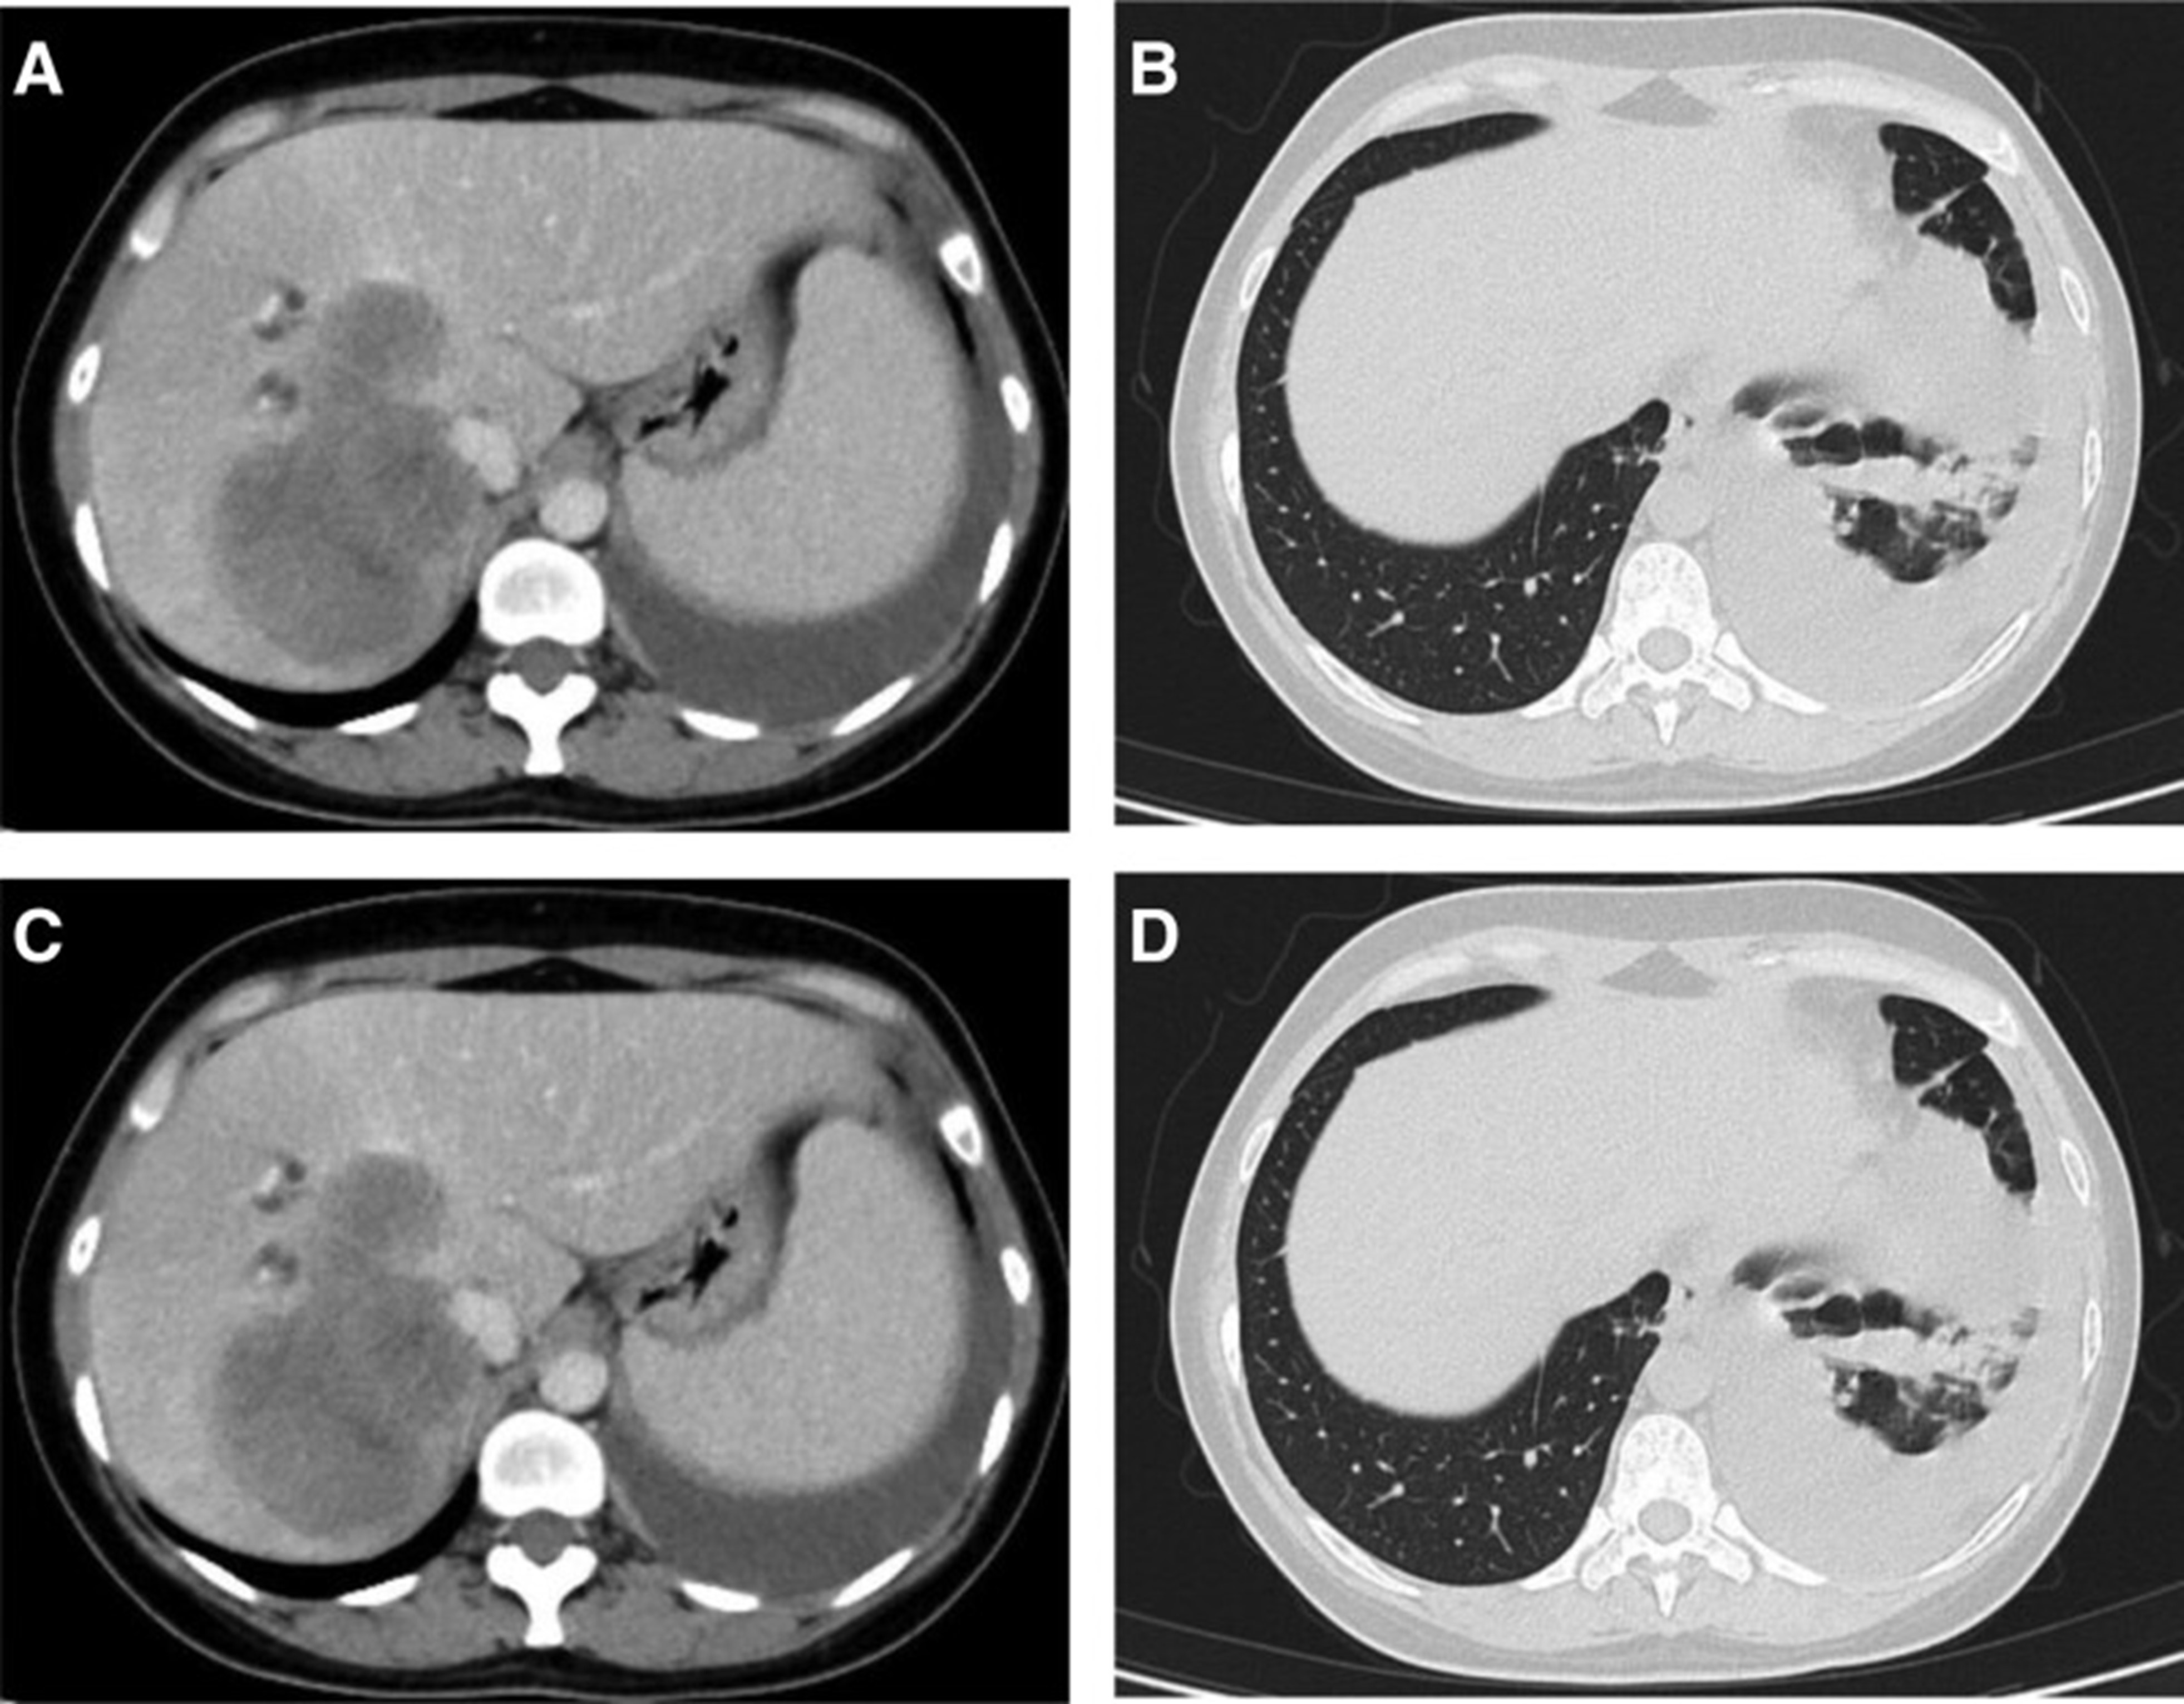

1个月后复查显示肺部和肝内病变进展(图1)。(图 6A-C)(根据RECIST1.1),她的抗肿瘤治疗改为“培姆曲塞加卡铂和贝伐单抗”的治疗一个周期。2020年12月至2021年1月,再次改变患者的治疗方案,这次改为“劳拉替尼联合达拉非尼”靶向治疗。使用 PD 联合胸部和腹部 CT 评估疗效(图 1)。(图 6D-F)(根据 RECIST1.1)。患者无法耐受化疗、靶向治疗、IO 治疗或任何其他积极的抗肿瘤治疗。这是因为患者的一般情况较差,包括发烧、腹痛和胆红素水平升高等症状。随后,给予患者静脉营养、镇痛等对症支持治疗。患者于 2021 年 2 月 4 日去世,总生存期(OS)为 10 个月。

和 2022 年 1 月 (D-F) 的 CT 扫描.jpg)

图 6:2020 年 11 月 (A-C) 和 2022 年 1 月 (D-F) 的 CT 扫描。CT = 计算机断层扫描。